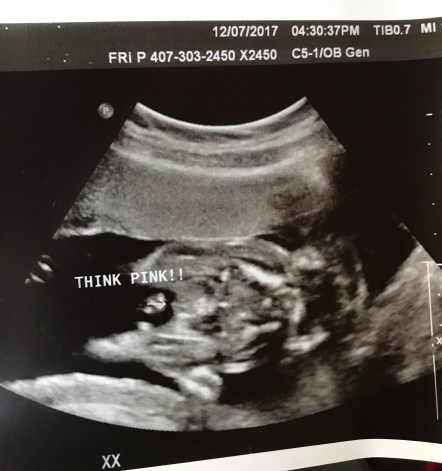

For my 20 week anatomy scan, I asked for the sonographer not to tell me the sex of my baby, but told her that I still wanted a photo revealing the baby’s gender to save for later for the scrapbook. They obliged and put the gender ultrasound picture in an envelope, stapled shut.

A few days later when things had (sort of) calmed down [read: when Matt had passed his Pediatrics end of rotation exam], we decided to pull the ultrasound photo out of the safe and put it in the scrapbook.

We were both utterly shocked to discover that I am one of the estimated 5% that was given the WRONG GENDER!!!!!!!!!!!!!!!!!!!!!!!!!!!!